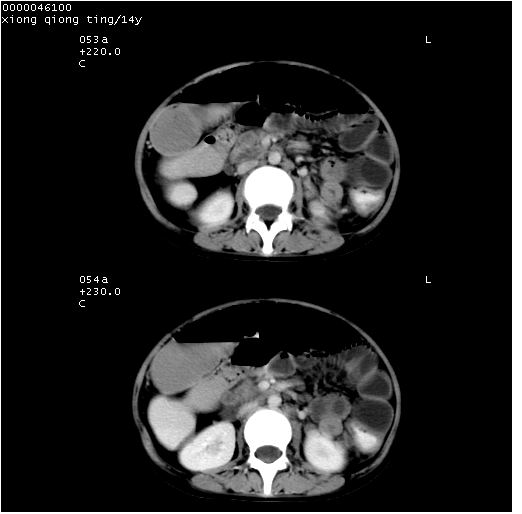

患儿 女,14岁。不规则发热一周,偶感头痛,无抽搐及呕吐。pe:神清,精神差,双侧瞳孔等大等圆,对光反射敏感,双肺未闻及明显啰音,心音有力,腹部触之似揉面感,下腹压痛,无反跳痛。

腹部b超提示:子宫缩小,盆腔积液,肝实质回声密集。

临床诊断:发热原因待查:1)腹部结核感染。2)伤寒?3)结缔组织病?

中下腹及盆腔ct轴位平扫+增强扫描(层厚10mm,螺距1.0,重建间隔10mm),图像如下:

(注:患儿检查当日上午9时口服胃肠道对比剂,下午3时许行ct扫描检查,未行对比剂直肠保留灌肠,检查当日患儿腹泻)

中下腹及盆腔ct轴位扫描(ps+ce)提示:腹部肠管明显充气扩张,并见数个不同宽度之气液平面;疑不全性肠梗阻或肠郁张。临床会诊考虑为患儿腹泻,肠郁张所致;后来未经特殊处理,患儿大便恢复正常,亦无腹胀。

临床出院诊断:1)结核性腹膜炎。2)腹膜后淋巴结结核。3)脂肪肝。